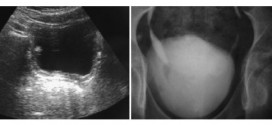

CARCINOMA VESICAL

El carcinoma vesical. La vejiga es un órgano que almacena la orina a baja presión, se vacía por completo de forma voluntaria y mantiene la continencia en los intervalos. Anatómicamente está formada por dos capas diferentes: una mucosa en contacto con la orina que se denomina urotelio y un músculo llamado detrusor, situado en profundidad y responsable de la contracción …